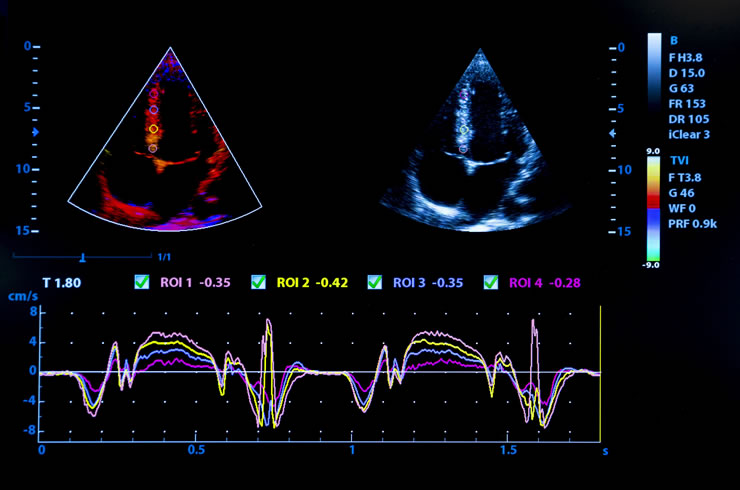

Υπέρηχος καρδίας

Ο υπέρηχος καρδιάς (cardiac echo) είναι μία μη επεμβατική καρδιολογική εξέταση η οποία χρησιμοποιεί την τεχνολογία των υπερήχων για τη δημιουργία εικόνων της καρδιάς σε πραγματικό χρόνο. Αυτή η τεχνική απεικόνισης είναι πολύτιμη για την αξιολόγηση της δομής και της λειτουργίας της καρδιάς, παρέχοντας λεπτομερείς πληροφορίες σχετικά με τις καρδιακές κοιλότητες, τις βαλβίδες και τις γύρω δομές.

Είναι μία από τις βασικές εξετάσεις που πραγματοποιούνται σε μία καρδιολογική επίσκεψη. Σε αντίθεση με ορισμένες άλλες τεχνικές καρδιακής απεικόνισης, ο υπέρηχος καρδιάς δεν περιλαμβάνει ακτινοβολία ή επεμβατικές διαδικασίες. Παρέχει άμεσες εικόνες, επιτρέποντας τη δυναμική αξιολόγηση της λειτουργίας της καρδιάς σε πραγματικό χρόνο.

Είναι ένα πολύτιμο διαγνωστικό εργαλείο που παίζει καθοριστικό ρόλο στην ολοκληρωμένη αξιολόγηση της καρδιακής υγείας και βοηθά στην καθοδήγηση των θεραπευτικών αποφάσεων. Χρησιμοποιείται συνήθως στην κλινική πράξη για ασθενείς με ένα ευρύ φάσμα καρδιαγγειακών παθήσεων.

Τα ηχητικά κύματα υψηλής συχνότητας (υπέρηχος), πέρα από το εύρος της ανθρώπινης ακοής, κατευθύνονται προς την καρδιά. Αυτά τα κύματα αναπηδούν από τις δομές της καρδιάς και η ηχώ που επιστρέφει συλλαμβάνεται από τον μορφοτροπέα.

Στη συνέχεια, τα δεδομένα που συλλέγονται υποβάλλονται σε επεξεργασία για τη δημιουργία εικόνων της καρδιάς σε πραγματικό χρόνο, εμφανίζοντας τη δομή, τη λειτουργία και τη ροή του αίματος της.